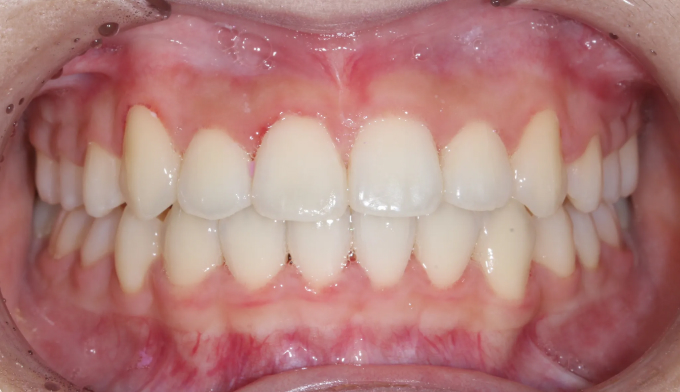

이번 케이스에서는 덧니가 심하고 공간이 매우 부족하지만, 입의 크기가 작고 입술이 얇은 편이었기 때문에 발치 없이 교정하기로 계획하였습니다.

입천장 확장과 치아배열을 통하여 총 18개월동안 치료하였습니다.